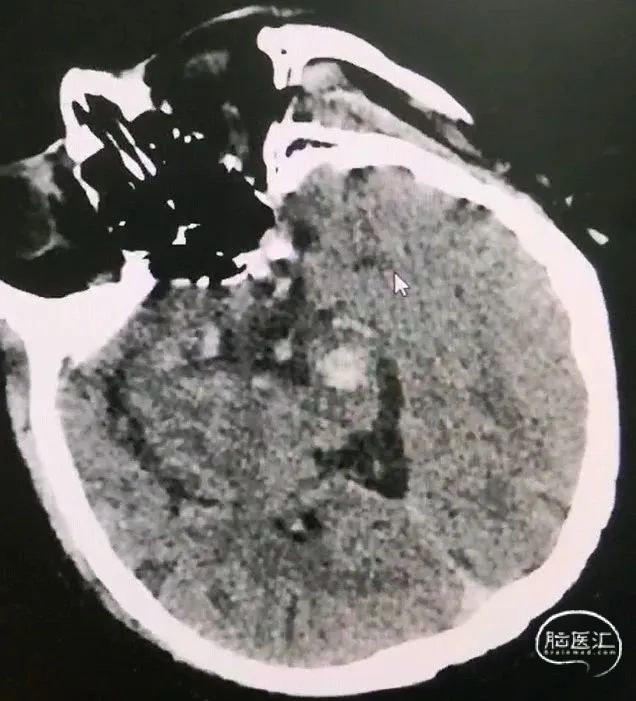

CT扫描后测算脑干血肿穿刺靶点及路径

引流管穿经中脑血肿

引流管准确到达靶点

术后尿激酶应用,术后3天复查CT,血肿引流满意